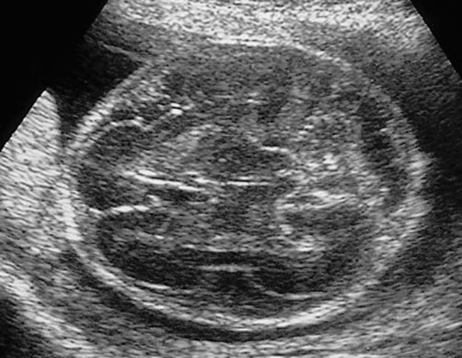

Pena-Shokeir Syndrome - Knees hyperextended, arms contracted and crossed over, Polyhydramnios, Micrognathia,